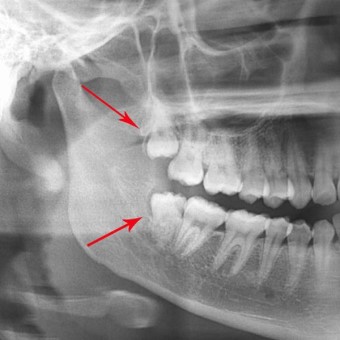

Răng khôn mọc ngang, mọc lệch: Sẽ đẩy vào răng số 7, gây ảnh hưởng cả hàm răng, có thể khiến chân răng số 7 bị ảnh hưởng, gây tiêu xương, viêm nhiễm hoặc nang chân răng

Răng khôn không thể mọc thoát ra ngoài, ngầm trong xương hàm: Sẽ hình thành nang quanh thân răng, nang quanh thân răng phát triển phá hủy toàn bộ xương góc hàm.

Bước 2: Chụp X-Quang phim panorama

Bước 3: Phân tích, đánh giá tình trạng răng và lựa chọn phương pháp nhổ răng